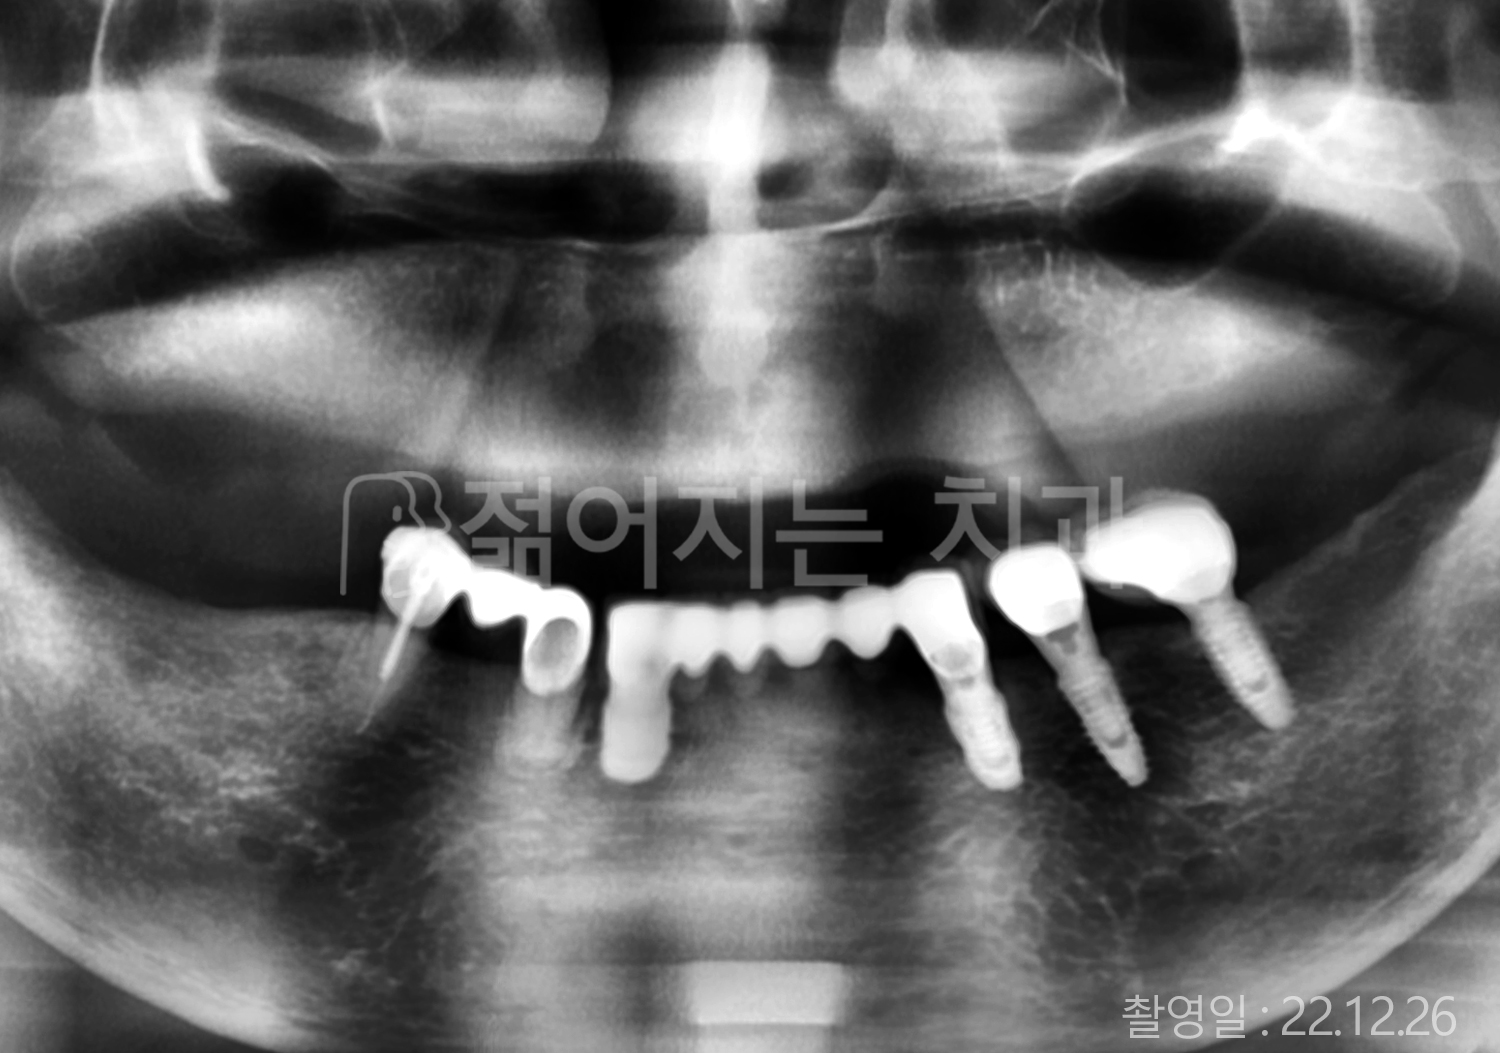

• 60대 고혈압, 고지혈증 전체치아 10개 이상 임플란트